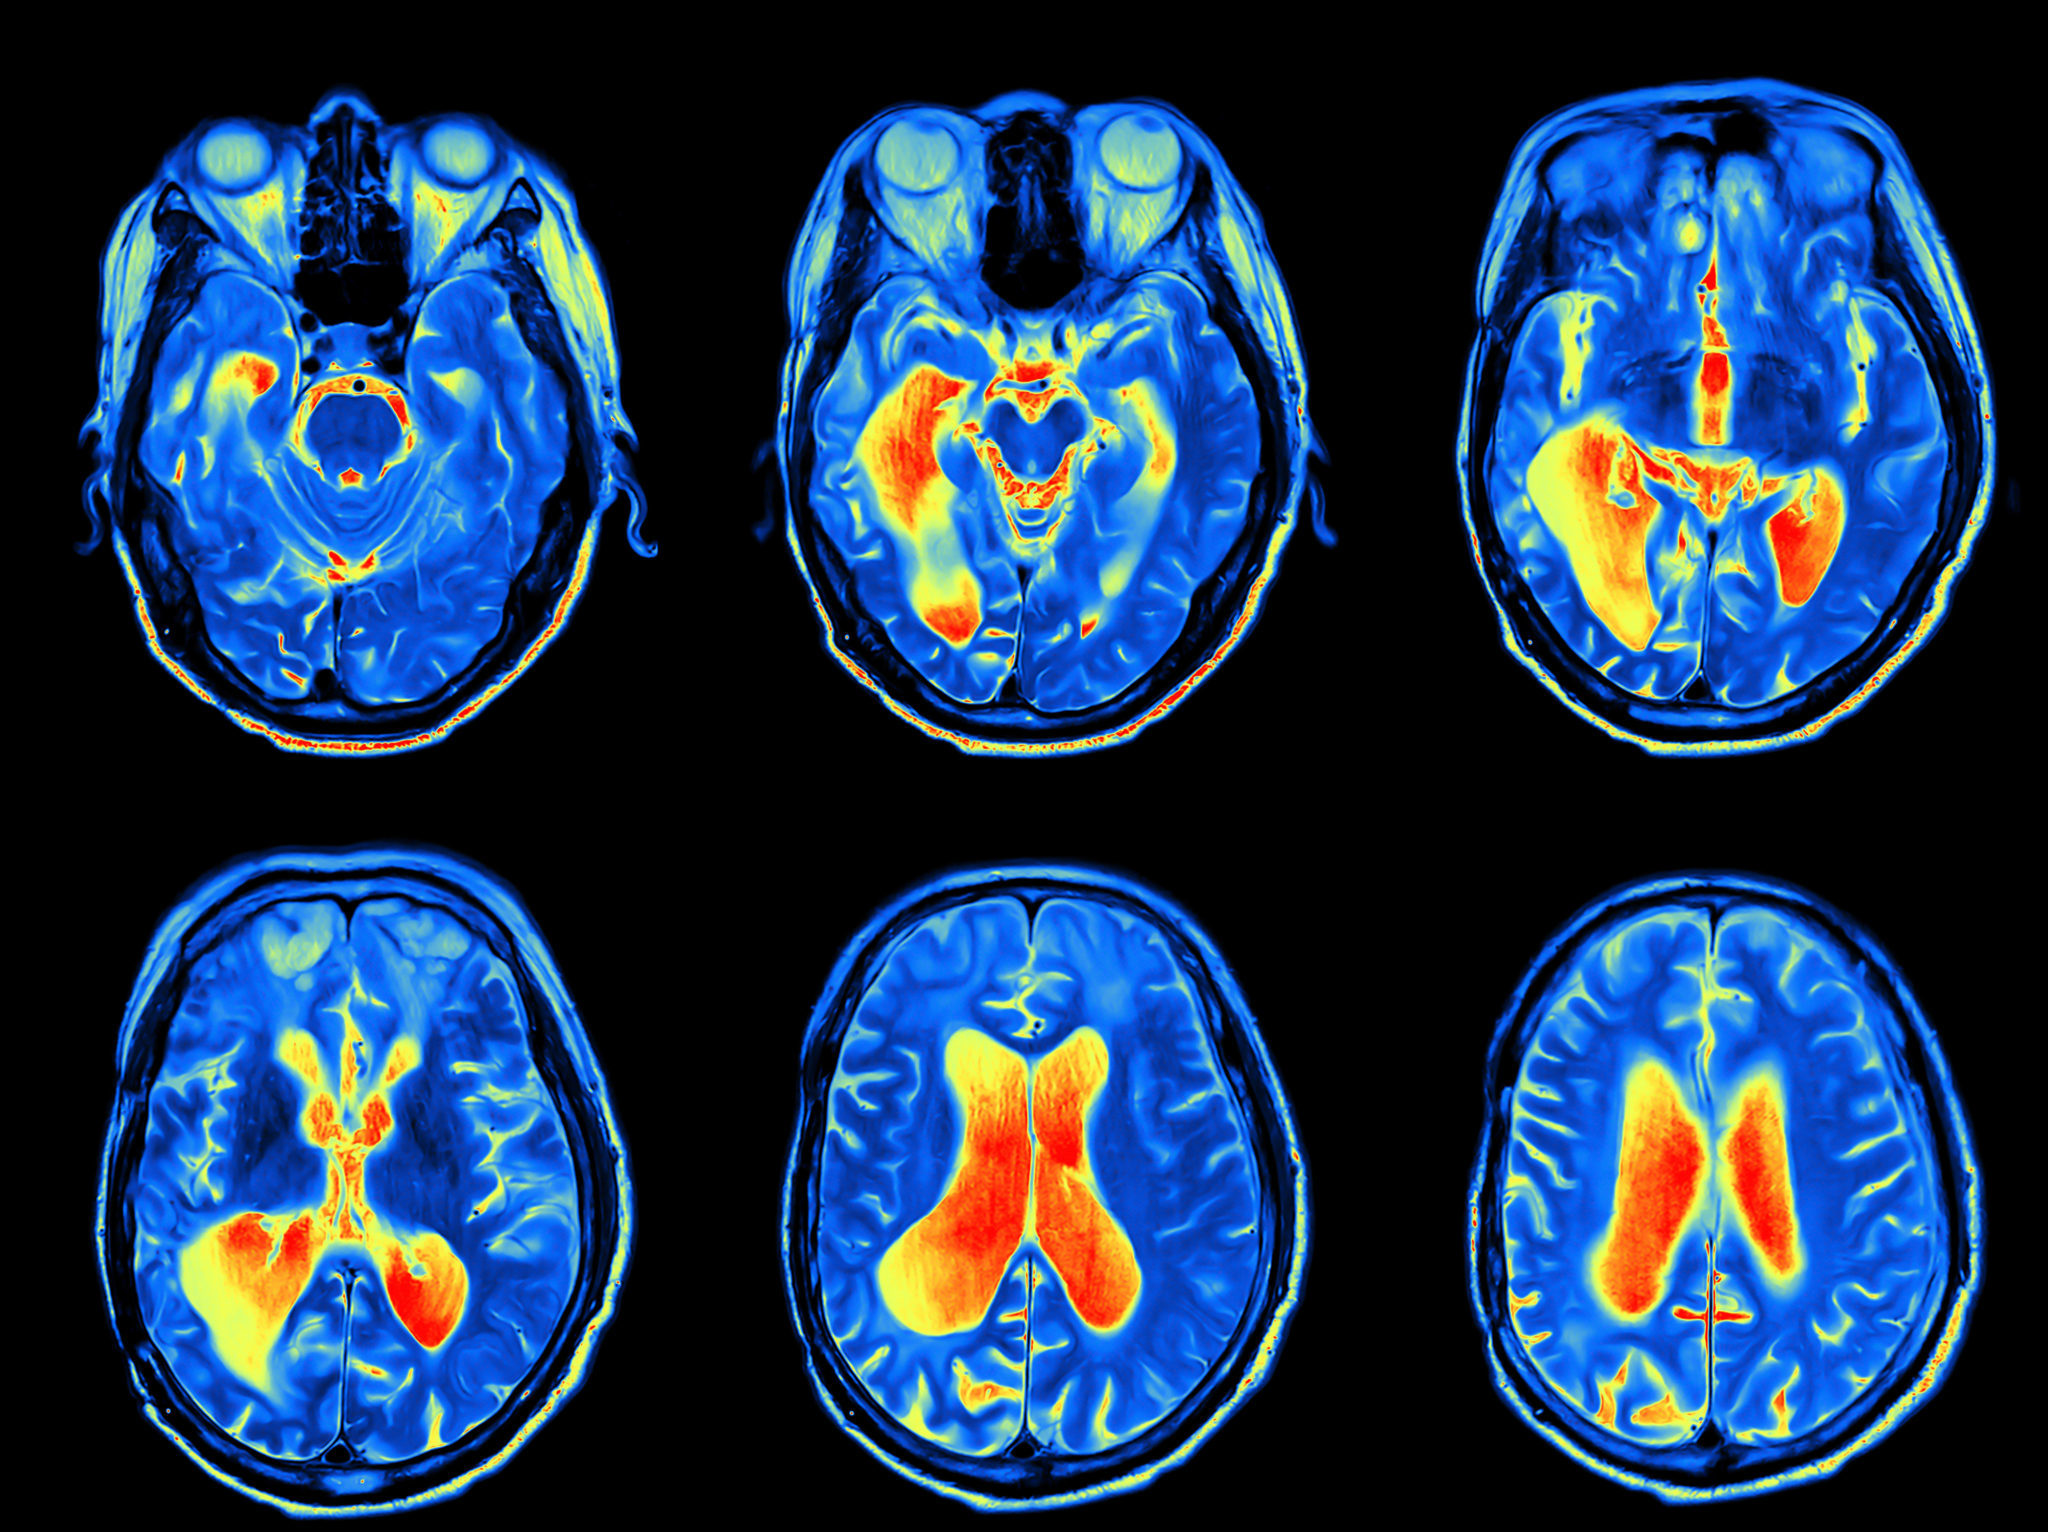

The hearing process begins with noises traveling from the outer ear, through the middle ear and into the inner ear where the noises cause thousands of tiny hair cells to vibrate. These hair cells send electrical signals to the auditory nerve that connects to the brain. After the signal travels through the nerve, it is sent to the brain where it is processed and translated into sounds that people can recognize and understand.

The newer brain hearing technology takes this idea to the next level by focusing devices on the brain instead of the ear. Researchers have learned that sound processing actually occurs in the brain and not the ear. Brain focused hearing devices work to preserve natural noise quality in speech recognition, spatial recognition, sound filtering and sound focusing.